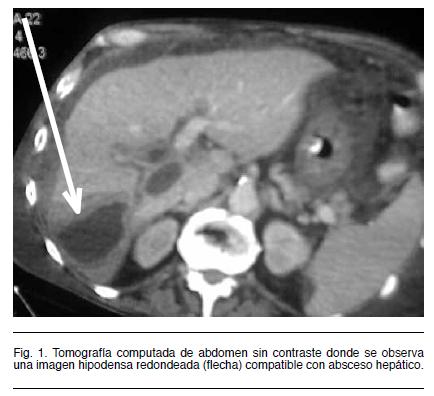

La angio-tomografía abdominal identifica dichas lesiones y evidencia trombosis de la vena porta y suprahepáticas, compatible con el diagnóstico de pileflebitis séptica (Figura 1 y 2).

Es de fundamental valor para el control evolutivo, pudiendo detecta recanalización o no del territorio portal, el desarrollo de cavernomatosis portal y signos de hipertensión portal. (7) La ecografía intraoperatoria es un método fiable para confirmar el diagnóstico y evaluar el grado de extensión de la trombosis. (12) La presencia de aire intraluminal indica enfermedad avanzada y es un elemento de mal pronóstico. La tomografía abdominal con angiotomografía es el estudio de elección, este revela la trombosis venosa porto-mesentérica, (Figura 2) mostrando un defecto en el relleno venoso con atenuación central, rodeado por el anillo de la pared venosa. Permite además evaluar la existencia de isquemia de la pared intestinal con una sensibilidad mayor al 90% y defectos de la circulación porto-mesentérica. (8,13) En el caso analizado el parénquima hepático mostró a nivel del lóbulo derecho áreas hipodensas con zonas hiperdensas mal definidas, con desplazamiento de vasos y periferia hipervascular compatible con abscesos múltiples. Además pueden coexistir microabscesos (no visualizables por esta técnica) y que por su tamaño no es posible drenar. (14)